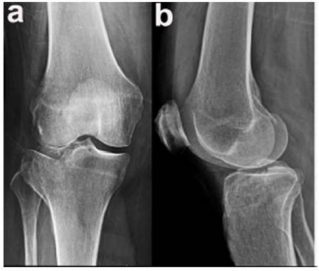

Caso clínico para responder à questão.

Um paciente de 39 anos de idade, vítima de queda de bicicleta, sofreu trauma no joelho direito. Foi levado ao pronto-socorro do hospital mais próximo, onde foram realizadas as radiografias apresentadas.